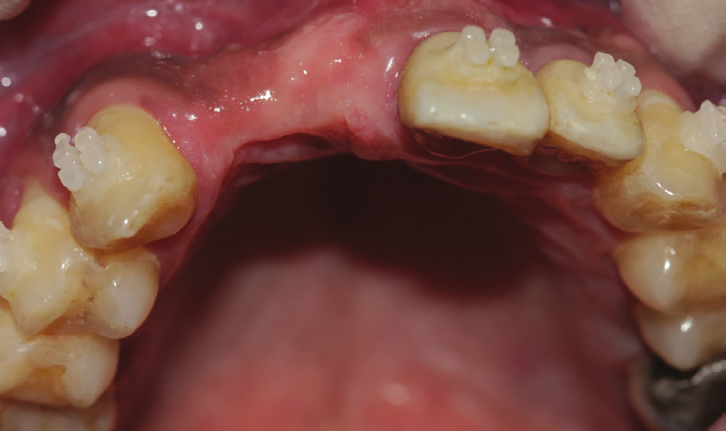

Figure 1: Preoperative intraoral view showing the ex- tended Maryland bridge compressing and replacing the loss of gum in the area.

Figure 2: Intraoral view showing the extended bone and gingival loss with recession on both central incisor and canine.

Figure 3: Occlusal intraoral view showing the advanced amount of bone loss.

Intraoral examination showed a bridge replacing sites no 26 and 25 with a gingival extension replacing the bone loss in the area (Fig.1). Extra oral examination was normal.

After removal of the bridge an extended bone loss was found. (Fig.2, 3). X-rays and CAT views were taken for the region. The amount of bone loss was extended which was an indication for autologous bone graft. A PRF associated bovine bone technique was planned. A linear incision with mucoperiosteal flap elevation was conducted. The adjacent teeth showed also bone loss (Fig.4).